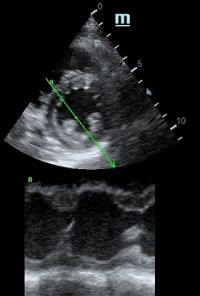

Но как же провести стандартные измерения в М-режиме, если мы его не использовали? На помощь приходит функция Free Xros M – анатомический М-режим. Имея записанную в память прибора видео петлю, мы можем провести линию М-режима в любом месте, при этом корректируя изначально не оптимальный угол.

TAPSE - показатель амплитуды движения латеральной части кольца трикуспидального клапана, позволяет количественно и быстро оценить систолическую функцию правого желудочка, норма которого составляет более 17 мм. Главным условием является проведение линии М-режима параллельно стенке правого желудочка в апикальном четырех камерном сечении, что легко достигается при Free Xros.